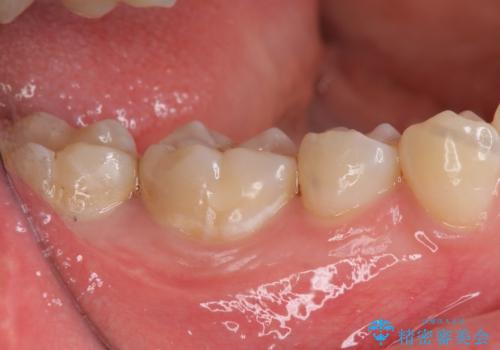

- 右下56 セラミックインレー 77000円×2本費用は治療当時の料金となります

メンテナンスで虫歯を発見することができたため、症状が出る前に治療を終えることができました。下の奥歯は笑った時に外からよく見える部分なので白く目立たない詰め物を入れることができて大変喜んでいただけました。

放置していくとインレーでの修復が難しくなってしまうため、定期的なメンテナンスが大事になってきます。